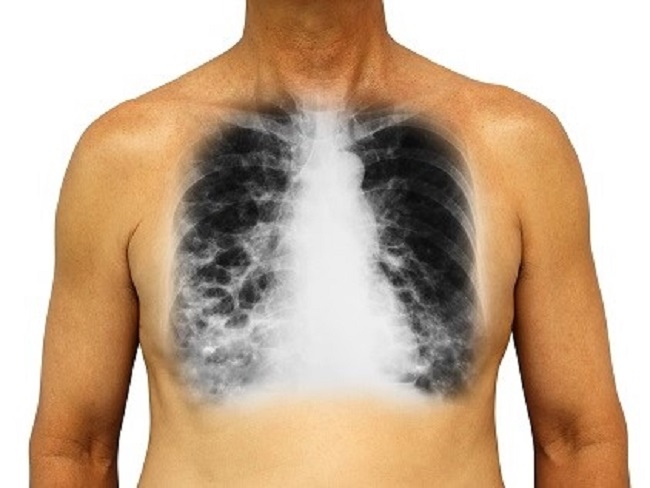

Sama seperti sistem organ yang lain sistem pernapasan pada manusia juga bisa mengalami gangguan atau kelainan yang mempengaruhi sistem itu sendiri. Adapun gejala-gelaja tonsilitis adalah sebagai berikut. Asma merupakan kelainan penyumbatan saluran pernapasan. Jika alat ini terganggu karena penyakit atau kelainan maka proses pernapasan akan terganggu bahkan dapat menyebabkan kematian.

Itu baik karena kelainan pada sistem pernapasan atau akibat infeksi kuman. Admin blog Sebutkan Mendetail 2019 juga mengumpulkan gambar-gambar lainnya terkait penyempitan saluran pernapasan karena alergi disebut dibawah ini. Tonsilitis umumnya disebabkan oleh infeksi virus dan bakteri. Emfisema paru-paru merupakan penyakityang gejala utamanya adalah penyempitan obstruksi saluran napas karena kantung udara di paru menggelembung. Asma merupakan kelainan penyumbatan saluran pernapasan.

Asma yaitu gangguan pernapasan karena penyempitan saluran pernapasan.

Inilah pembahasan lengkap terkait penyempitan saluran pernapasan karena alergi disebut. Ada beberapa jenis gangguan pada sistem pernapasan manusia yang harus kamu ketahui yakni. Penyempitan atau penyumbatan saluran napas dapat disebabkan oleh pembengkakan kelenjar limfa misalnya polip di hidung dan amandel di tekak yang menyebabkan penyempitan saluran pernapasan sehingga menimbulkan kesan wajah bodoh dan sering disebut wajah adenoid. Asma adalah suatu keadaan di mana saluran nafas mengalami penyempitan karena hiperaktivitas terhadap rangsangan tertentu yang menyebabkan peradangan.

Gejala khas yang umumnya dialami penderita asma adalah mengi sesak napas dada terasa sesak dan batuk. Gangguan karena penyempitan atau penyumbatan saluran pernapasan ini salah satu kelainan sistem pernapasan yang di sebabkan karna. Emfisema paru-paru merupakan penyakityang gejala utamanya adalah penyempitan obstruksi saluran napas karena kantung udara di paru menggelembung. Keluhan ini membuat saluran napas mengalami penyempitan.

Dikutip situs Kementerian Pendidikan dan Kebudayaan Kemendikbud sistem pernapasan dapat mengalami berbagai gangguan. Udara yang tercemar oleh asap dan debu. Gejala khas yang umumnya dialami penderita asma adalah mengi sesak napas dada terasa sesak dan batuk. Asma merupakan gangguan respirasi yang ditandai dengan peradangan pada saluran pernapasan. Jika terjadi infeksi melalui mulut atau saluran pernapasan tonsil akan membengkak radang yang dapat menyebabkan penyempitan saluran pernapasan.

Jika terjadi infeksi melalui mulut atau saluran pernapasan tonsil akan membengkak radang yang dapat menyebabkan penyempitan saluran pernapasan. Sistem pernapasan pada manusia adalah salah satu sistem organ yang sangat penting. Pembengkakan kelenjar limfemengarah ke wajah adenoid mulut terbuka untuk membantu bernapas polip pada rongga hidung dan amandel pada tekak. Asma yaitu gangguan pernapasan karena penyempitan saluran pernapasan. Emfisema paru-paru merupakan penyakityang gejala utamanya adalah penyempitan obstruksi saluran napas karena kantung udara di paru menggelembung.